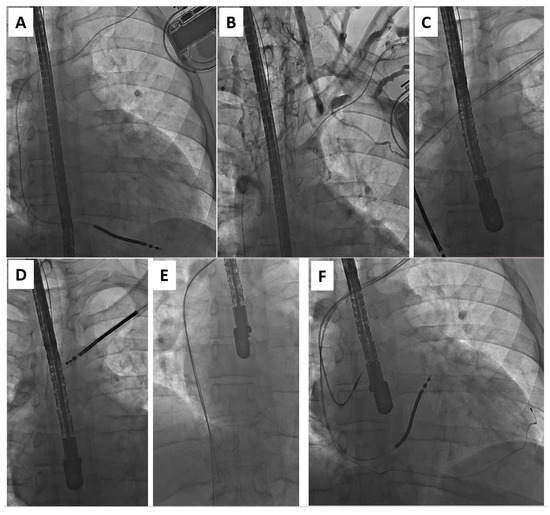

Zero-Fluoroscopy Catheter Ablation of Right Appendage Focal Atrial Tachycardia in a Pregnant Woman

Clin. Pract. 2024, 14(3), 946-953; https://doi.org/10.3390/clinpract14030075 - 21 May 2024

Background: Arrhythmias in pregnancy are complex to manage due to the teratogenic effects of many antiarrhythmic drugs and the common use of ionizing radiation during catheter ablation procedures. Furthermore, pregnant women are extremely vulnerable and difficult to treat because of the progressive physical [...] Read more.

Background: Arrhythmias in pregnancy are complex to manage due to the teratogenic effects of many antiarrhythmic drugs and the common use of ionizing radiation during catheter ablation procedures. Furthermore, pregnant women are extremely vulnerable and difficult to treat because of the progressive physical and hormonal changes that occur during the nine months of pregnancy. Case Presentation: In this case report, we describe a complex clinical case of a 34-year-old pregnant woman who was affected by an incessant right atrial tachycardia, with signs and symptoms of initial hemodynamic instability. This tachycardia was refractory to antiarrhythmic drugs, so a zero-fluoroscopy ablation was performed. The first procedure was complicated by cardiac tamponade, quickly resolved without further complications for the mother or the fetus. In the following days, a deep venous thrombosis occurred at the femoral venous access. After a few days, the patient underwent a second procedure that was successful and resulted in the restoration of a sinus rhythm. Conclusions: The management of this clinical case was complex both from a procedural and a clinical (cardiological and gynecological) point of view. Finally, the integration of the various skills led to an excellent result. Full article